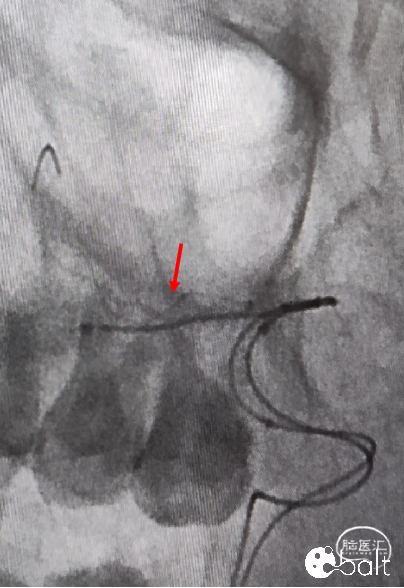

3、第一条支架全放,微导管穿支架网孔半释放另一条支架后填圈。

第二枚支架半释放至覆盖剩余部分瘤颈,为填圈做准备。

05